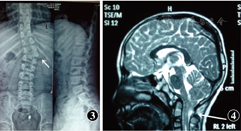

患儿,男,11岁,因出生后右眼内斜2014年2月11日于暨南大学附属深圳眼科医院就诊。足月剖宫产,既往无特殊病史。全身体检发现右手大鱼际肌肉萎缩,肌力4级,弱于对侧(图1),脊柱向右侧弯。检查:右眼第一眼位时上睑遮盖角膜缘约3 mm,睑裂较左眼略小,向右侧水平方向注视时睑裂变大,高度约为7 mm,内转时睑裂高度约为4 mm并伴眼球后退(图2)。代偿头位脸部向左偏斜。余双眼检查无异常,视力1.0。脊柱X射线检查:胸椎和腰椎正侧位可见胸腰段交界处脊柱右弯,胸腰段以T11-L1椎体为中心呈"S"形扭曲;L1椎体右半部阙如,左半部呈三角状并与T12相连(图3)。颅脑MRI示:T2WI矢状位见小脑扁桃体经枕骨大孔下移至颈部上缘椎管内1.5 cm,延髓略受压向前下方移位,齿状突位于钱氏线上1.1 cm,寰齿间隙异常增宽,伴周围异常低信号区,颈段脊髓中央管呈喇叭样异常扩张,平C7水平,脊髓中央管内可见片状稍高信号影,提示脑部先天发育畸形,符合Chiari-Ⅰ型畸形(图4)。根据患儿的临床表现及辅助检查结果,诊断为Duane桡骨线综合征(Duane radial ray syndrome,DRRS)合并Chiari-Ⅰ型畸形。

Arnold-Chiari畸形是于1891年首次报道的以颅后窝容积缩小、小脑扁桃体向下进入椎管腔为主要病理学特征的先天性发育畸形[4],临床表现无特异性,颅脑MRI显示矢状位小脑扁桃体下疝5 mm以上可确诊本病及其伴发的脊髓空洞[5,6,7]:本例患者颅脑MRI显示小脑扁桃体下疝至枕骨大孔下方长达15 mm,符合Chiari-Ⅰ型畸形诊断。国内外有2例DRS伴Chiari-Ⅰ型畸形的病例报道,分别为Yamanouchi等[8]发现的1例13岁女性患儿和Prats等[9]发现的1例14岁女性患儿。